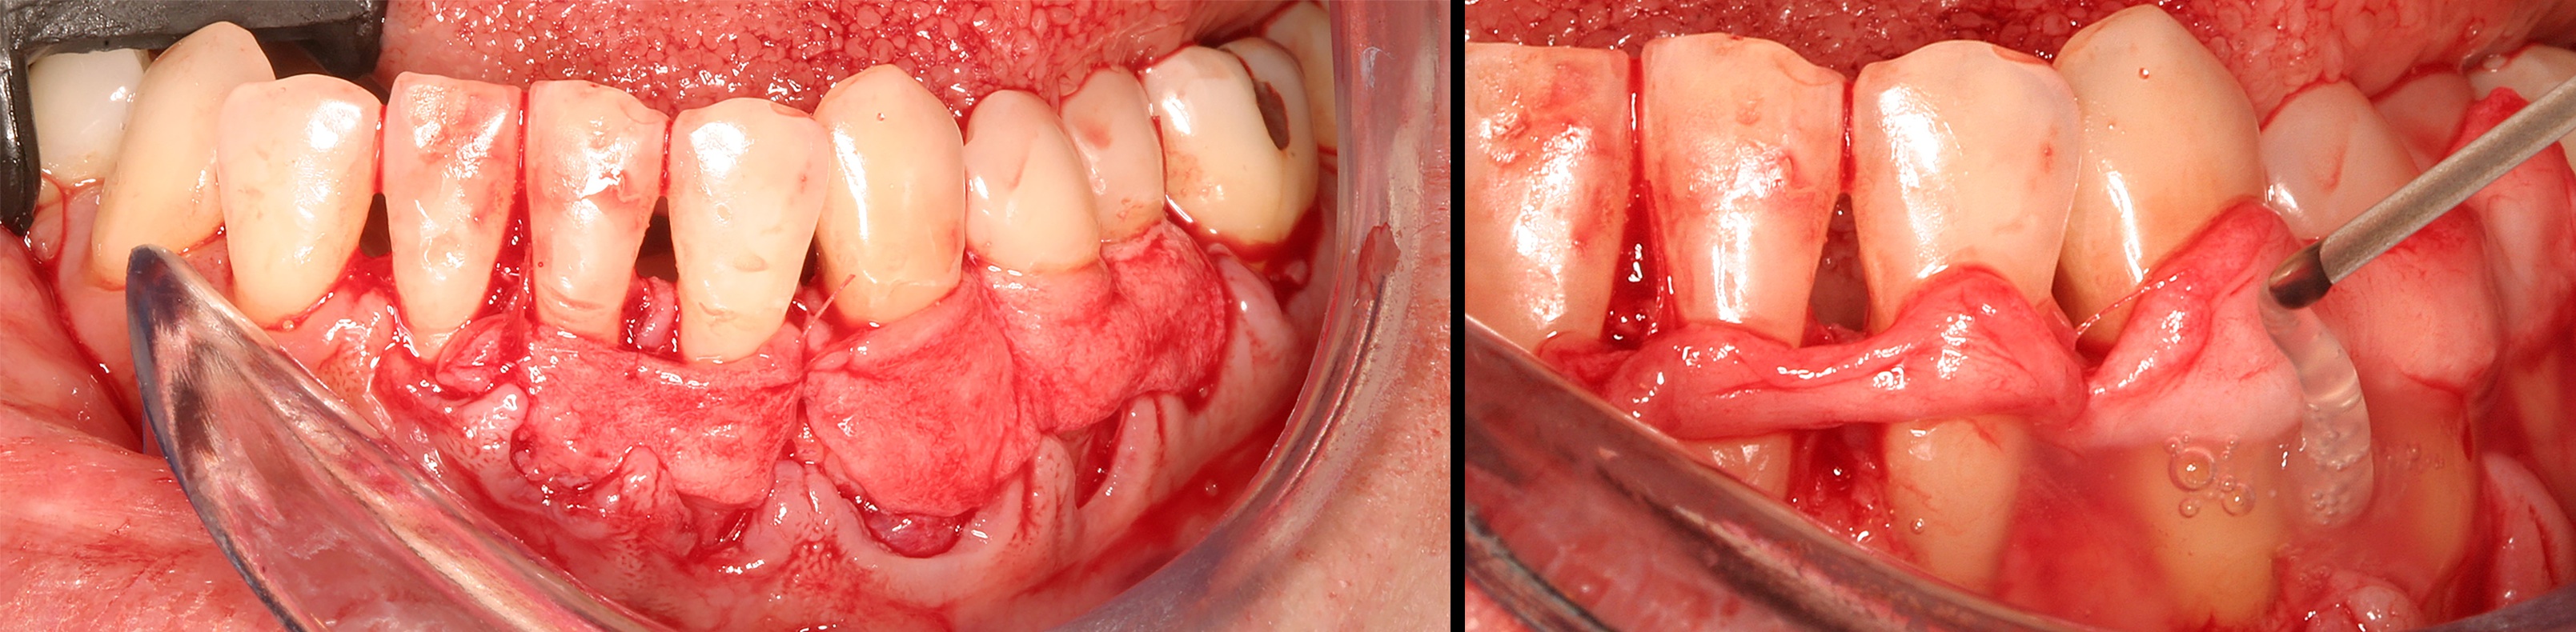

In the coming decades, restorative treatment for aging patients who experience facial growth with recession and erosion below the cemento-enamel junction because of tooth movement may be especially challenging. However, if dentists can employ the tenets of regeneration using autogenous tissues or a cellular dermal matrix combined with enamel matrix derivatives as a regulatory protein, they may predictably achieve large amounts of root coverage with thickened periodontium. This would not eliminate the need for restorative dentistry, but would enable restorative dentists to place restorations that are supragingival and are easily accessible for the patient and the therapist during maintenance (Figure 8 through Figure 10).

Preoperative recession.

Fig. 8

Acellular dermal graft combined with enamel matrix derivative.

Fig. 9

The 2.5-year postoperative photograph.

Fig. 10